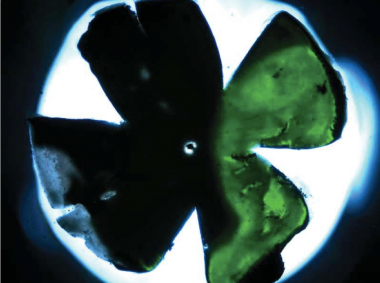

Flat mount of mouse retina showing delivery of transgene (green fluorescence).

Humans and mice with specific mutations in the BBS1 gene show progressive death of photoreceptor cells. In research recently published in Investigative Ophthalmology and Visual Sciences, Wynn Institute scientists made a virus containing a normal version of the mouse Bbs1 gene and injected the virus under the retina of mutant mice. When compared to untreated mice and untreated eyes in the same mice, the treated mice showed modest improvement in electrical responses in the retina and also showed partial restoration of normal retinal biochemistry. Ongoing studies will be needed to optimize the dose and type of virus, but this work offers hope that gene therapy for Bardet-Biedl Syndrome may eventually be effective in human patients.